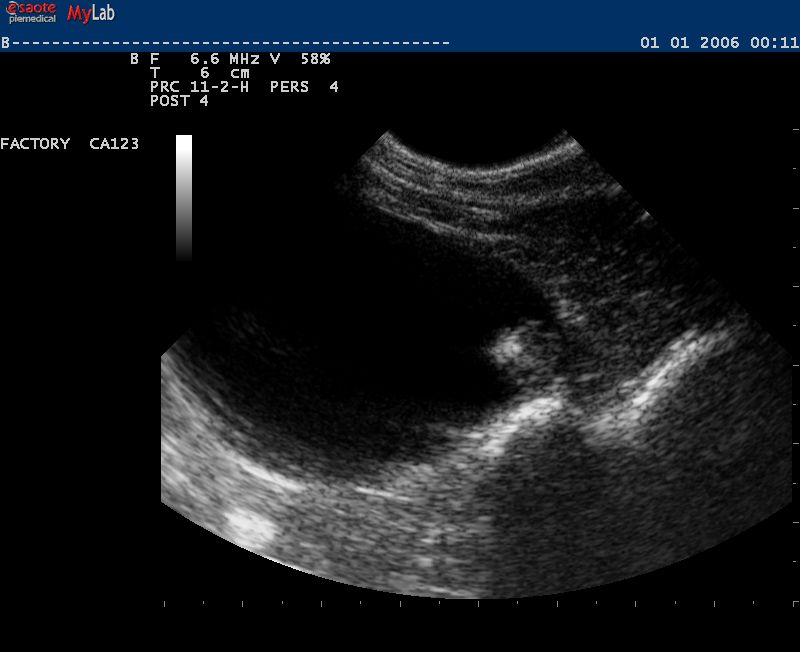

Auch in der Veterinärmedizin wird das schonende Verfahren der Ultraschalldiagnostik zunehmend eingesetzt. Wir verwenden es im Bereich der Abdominal- und Trächtigkeitsdiagnostik .